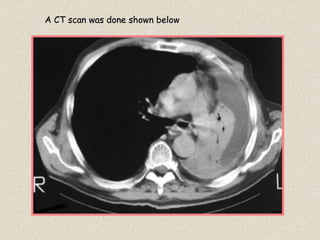

History: Patient with shortness of breath. A CXR is shown

Case 26

RADIOGRAPHIC FINDINGS:

1: Total opacification of left hemithorax

2: Shift of mediastinum to the left

DIFFERENTIAL DIAGNOSIS

1: Collapse of lung due to endobronchial obstructing lesion

2: Previous total pneumonectomy

A CT scan was done shown below

Diagnosis:

Complete collapse of Left lung.

Etiology: Large bronchogenic carcinoma